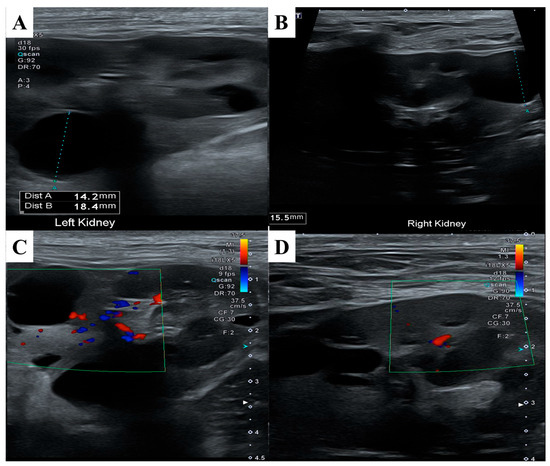

ND has been reported in association with renal cystadenomas or cystadenocarcinomas, and nodular lesions may also develop in other internal organs. To assess potential visceral involvement, an abdominal ultrasonographic examination was performed (Figure 4). Ultrasound evaluation revealed multiple round, smoothly marginated, anechoic cystic structures confined to the renal parenchyma of both kidneys. Most cysts exhibited distal acoustic enhancement and mildly distorted the renal contour.

Several cysts in the cranial pole of the left kidney displayed internal septations while remaining anechoic. One cyst in the mid-region of the right kidney showed mildly increased internal echogenicity but remained sharply marginated, with no vascular flow detected on color doppler imaging. No other ultrasonographic abnormalities were identified in the remaining abdominal organs.

Figure 4. Abdominal ultrasonography findings of the kidneys. (A) Anechoic, thin-walled, well-marginated cystic structures were observed within and around the parenchyma of the left kidney. (B) Similar cystic structures were noted in the right kidney. (C) Color doppler imaging of the left kidney revealed no vascular flow within the cysts. (D) Color doppler imaging of the right kidney also showed no detectable vascular flow, supporting the benign nature of the cysts.